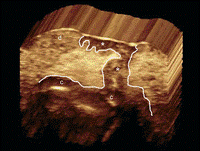

This area of investigation will likely be challenging. As noted earlier, the most obvious spatially heterogeneous imaging feature in tumors is perfusion heterogeneity on contrast-enhanced CT or MR images. It generally has been assumed that the links between contrast enhancement, blood flow, perfusion, and tumor cell characteristics are straightforward. That is, tumor regions with decreased blood flow will exhibit low perfusion, low cell density, and high necrosis. In reality, however, the dynamics are actually much more complex. As shown in Figure 4, when using multiple superimposed sequences from MR imaging of malignant gliomas, regions of tumor that are poorly perfused on contrast-enhanced T1-weighted images may exhibit areas of low or high water content on T2-weighted images and low or high diffusion on diffusion-weighted images. Thus, high or low cell densities can coexist in poorly perfused volumes, creating perfusion-diffusion mismatches. Regions with poor perfusion with high cell density are of particular clinical interest because they represent a cell population that is apparently adapted to microenvironmental conditions associated with poor perfusion. The associated hypoxia, acidosis, and nutrient deprivation select for cells that are resistant to apoptosis and thus are likely to be resistant to therapy (46,47).

Figure 4: Left: Contrast-enhanced T1 image from subject TCGA-02-0034 in The Cancer Genome Atlas–Glioblastoma Multiforme repository of MR volumes of glioblastoma multiforme cases. Right: Spatial distribution of MR imaging–defined habitats within the tumor. The blue region (low T1 postgadolinium, low fluid-attenuated inversion recovery) is particularly notable because it presumably represents a habitat with low blood flow but high cell density, indicating a population presumably adapted to hypoxic acidic conditions.

A method for converting images to spatially explicit tumor habitats is shown in Figure 4. Here, three-dimensional MR imaging data sets from a glioblastoma are segmented. Each voxel in the tumor is defined by a scale that includes its image intensity in different sequences. In this case, the imaging sets are from (a) a contrast-enhanced T1 sequence, (b) a fast spin-echo T2 sequence, and (c) a fluid-attenuated inversion-recovery (or FLAIR) sequence. Voxels in each sequence can be defined as high or low based on their value compared with the mean signal value. By using just two sequences, a contrast-enhanced T1 sequence and a fluid-attenuated inversion-recovery sequence, we can define four habitats: high or low postgadolinium T1 divided into high or low fluid-attenuated inversion recovery. When these voxel habitats are projected into the tumor volume, we find they cluster into spatially distinct regions. These habitats can be evaluated both in terms of their relative contributions to the total tumor volume and in terms of their interactions with each other, based on the imaging characteristics at the interfaces between regions. Similar spatially explicit analysis can be performed with CT scans (Fig 5).